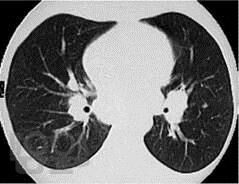

Учебное пособие предназначено для ординаторов, обучающихся по специальности 31.08.49 Терапия и слушателей дополнительного профессионального образования. В настоящем учебном пособии изложены современные представления по распространенности, этиологии, патогенезу, клинике, диагностике, дифференциальной диагностике и лечению саркоидоза органов дыхания, кожных покровов, почек, кардиального и костно-мышечного саркоидоза. Имеются тестовые задания и ситуационные задачи для самоконтроля знаний, издание иллюстрировано рисунками, схемами и таблицами.